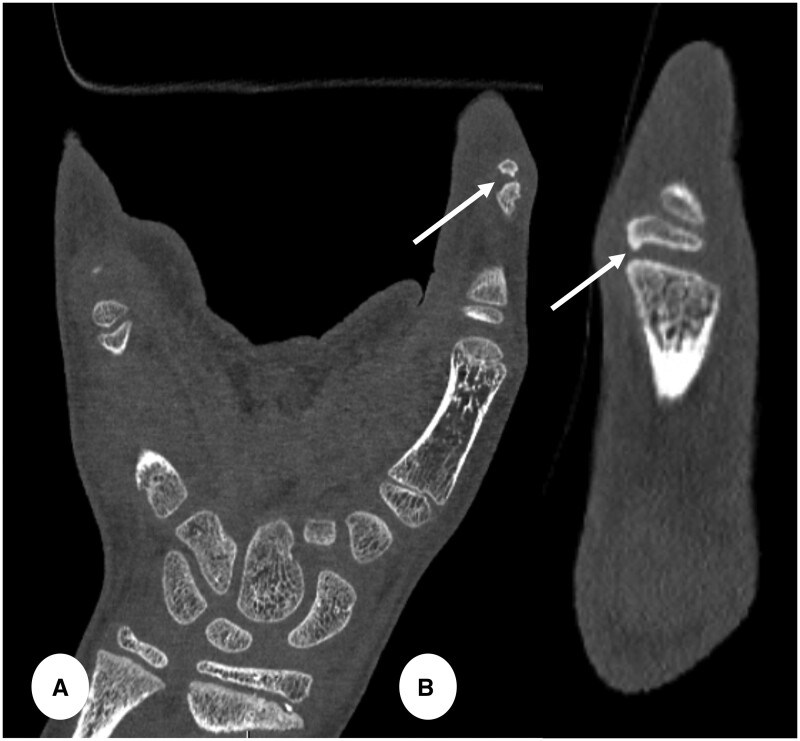

Recent advancements in CT technology have introduced a revolutionary innovation to practice known as the Photon-Counting detector (PCD) CT imaging. The pivotal hardware enhancement of the PCD-CT scanner lies in its detectors, which consist of smaller pixels than standard detectors and allow direct conversion of individual X-rays to electrical signals. As a result, CT images are reconstructed at higher spatial resolution (as low as 0.2 mm) and reduced overall noise, at no expense of an increased radiation dose. These features are crucial for paediatric imaging, especially for infants and young children, where anatomical structures are notably smaller than in adults and in whom keeping dose as low as possible is especially relevant. Since January 2022, our hospital has had the opportunity to work with PCD-CT technology for paediatric imaging. This pictorial review will showcase clinical examples of PCD-CT imaging in children. The aim of this pictorial review is to outline the potential paediatric applications of PCD-CT across different anatomical regions, as well as to discuss the benefits in utilizing PCD-CT in comparison to conventional standard energy integrating detector CT.